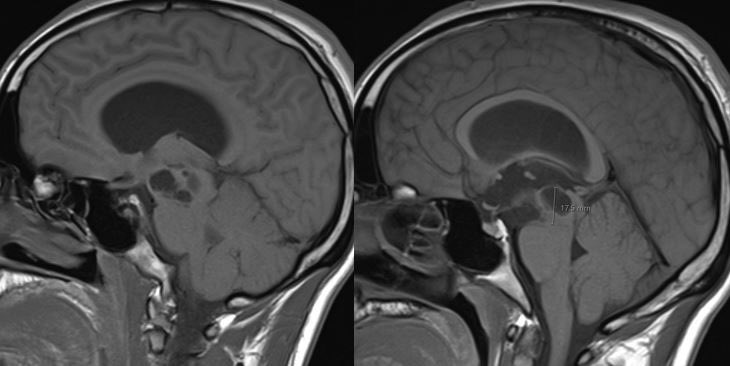

What is the most likely diagnosis in this 30 y/o M presenting with headaches? 🧠